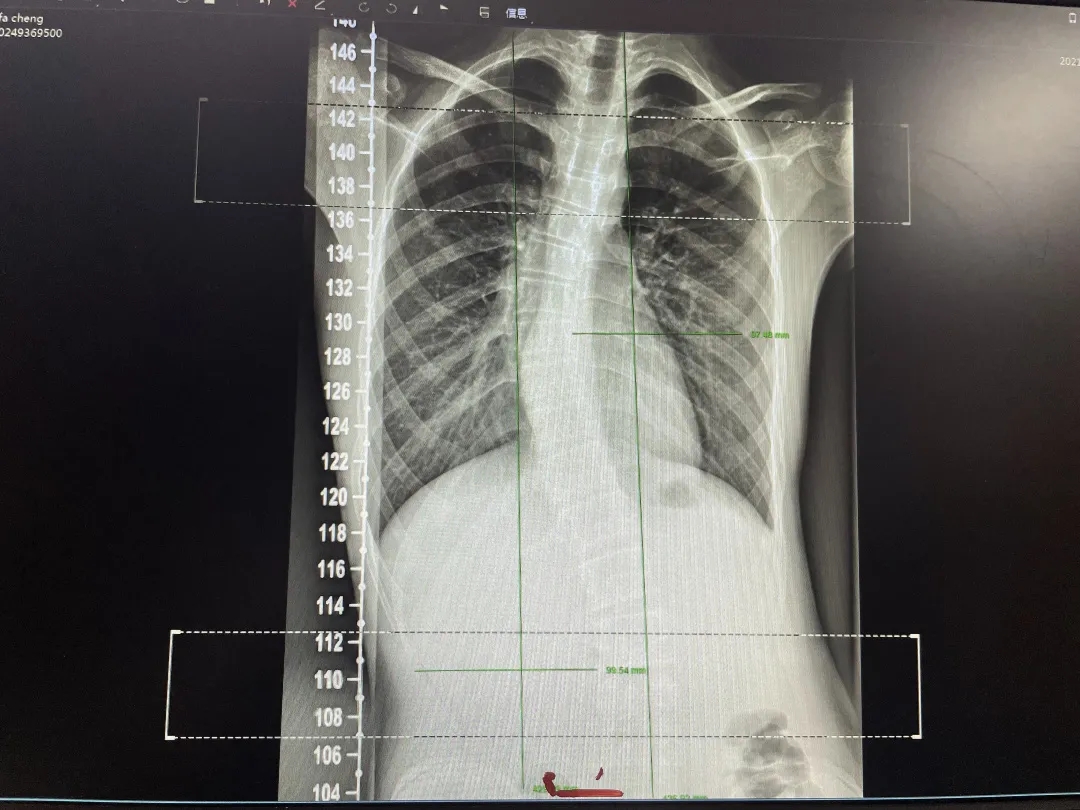

康复治疗前X光检查

今年13岁的小明在康复医学科门诊诊查中发现患有轻度脊柱侧弯。经过康复评定后,发现小明的脊柱发生“S型”侧弯且伴随着一定程度的旋转,造成小明驼背、高低肩、长短腿、脖子倾斜、翼状肩等不良体态。非先天性的脊柱侧弯主要原因是长期的不良生活习惯与不良姿势,从而引起一侧肌肉过于紧张,另一侧肌肉力量不足,最终引起脊柱的侧向弯曲或旋转。针对这一原理,康复医学科李新洲主任通过治疗松解脊柱旁紧张肌群,同时为小明进行骨盆与脊柱的整复,将骨盆与脊柱恢复到正常的生理解剖位置。